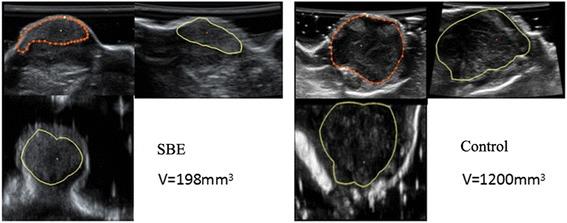

SBE treatment inhibited the proliferation of HepG2 cells in vitro with a dose-dependent manner and significantly suppressed the tumor growth of hepatoma H22-bearing mice. Meanwhile, it increased NK cells' cytotoxicity in spleen, down-regulated the amount of CD4CD25Foxp3 Treg cells and Th17 cells in tumor tissue, and decreased IL-10, TGF-β, and IL-17A levels (P < 0.01) whereas increased IL-2 and IFN-γ levels (P < 0.01) in the serum of hepatoma H22-bearing mice. Moreover, administration of recombinant mouse IL-17A reversed the anti-tumor effects of SBE.

SBE处理以剂量依赖的方式抑制体外HepG2细胞的增殖,并显著抑制荷肝癌H22小鼠的肿瘤生长。同时,它增加了脾脏NK细胞的细胞毒性,下调了肿瘤组织中CD4CD25Foxp3 Treg细胞和Th17细胞的数量,并降低了荷肝癌H22小鼠血清中IL-10、TGF-β和IL-17A的水平(P<0.01),而增加了IL-2和IFN-γ的水平(P<0.01)。此外,给予重组小鼠IL-17A可逆转SBE的抗肿瘤作用。